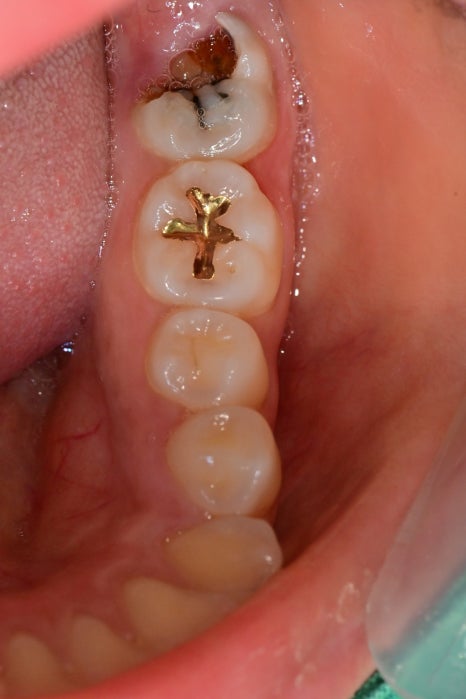

사진으로만 보아도

이미 충치가 진행이 신경까지 진행된 상태이며

약해진 치아는 쉽게 부서지고, 깨지는데

그 공간으로 잇몸이 차오른 것을 볼 수 있습니다.

이렇게 잇몸 안쪽까지 충치가 생긴 것은

신경치료를 먼저 꼼꼼하게 한 후

나중에 보철치료를 할 때 잇몸을 적절하게 성형을 하여

진행해야 제작하고, 관리하기가 수월합니다.